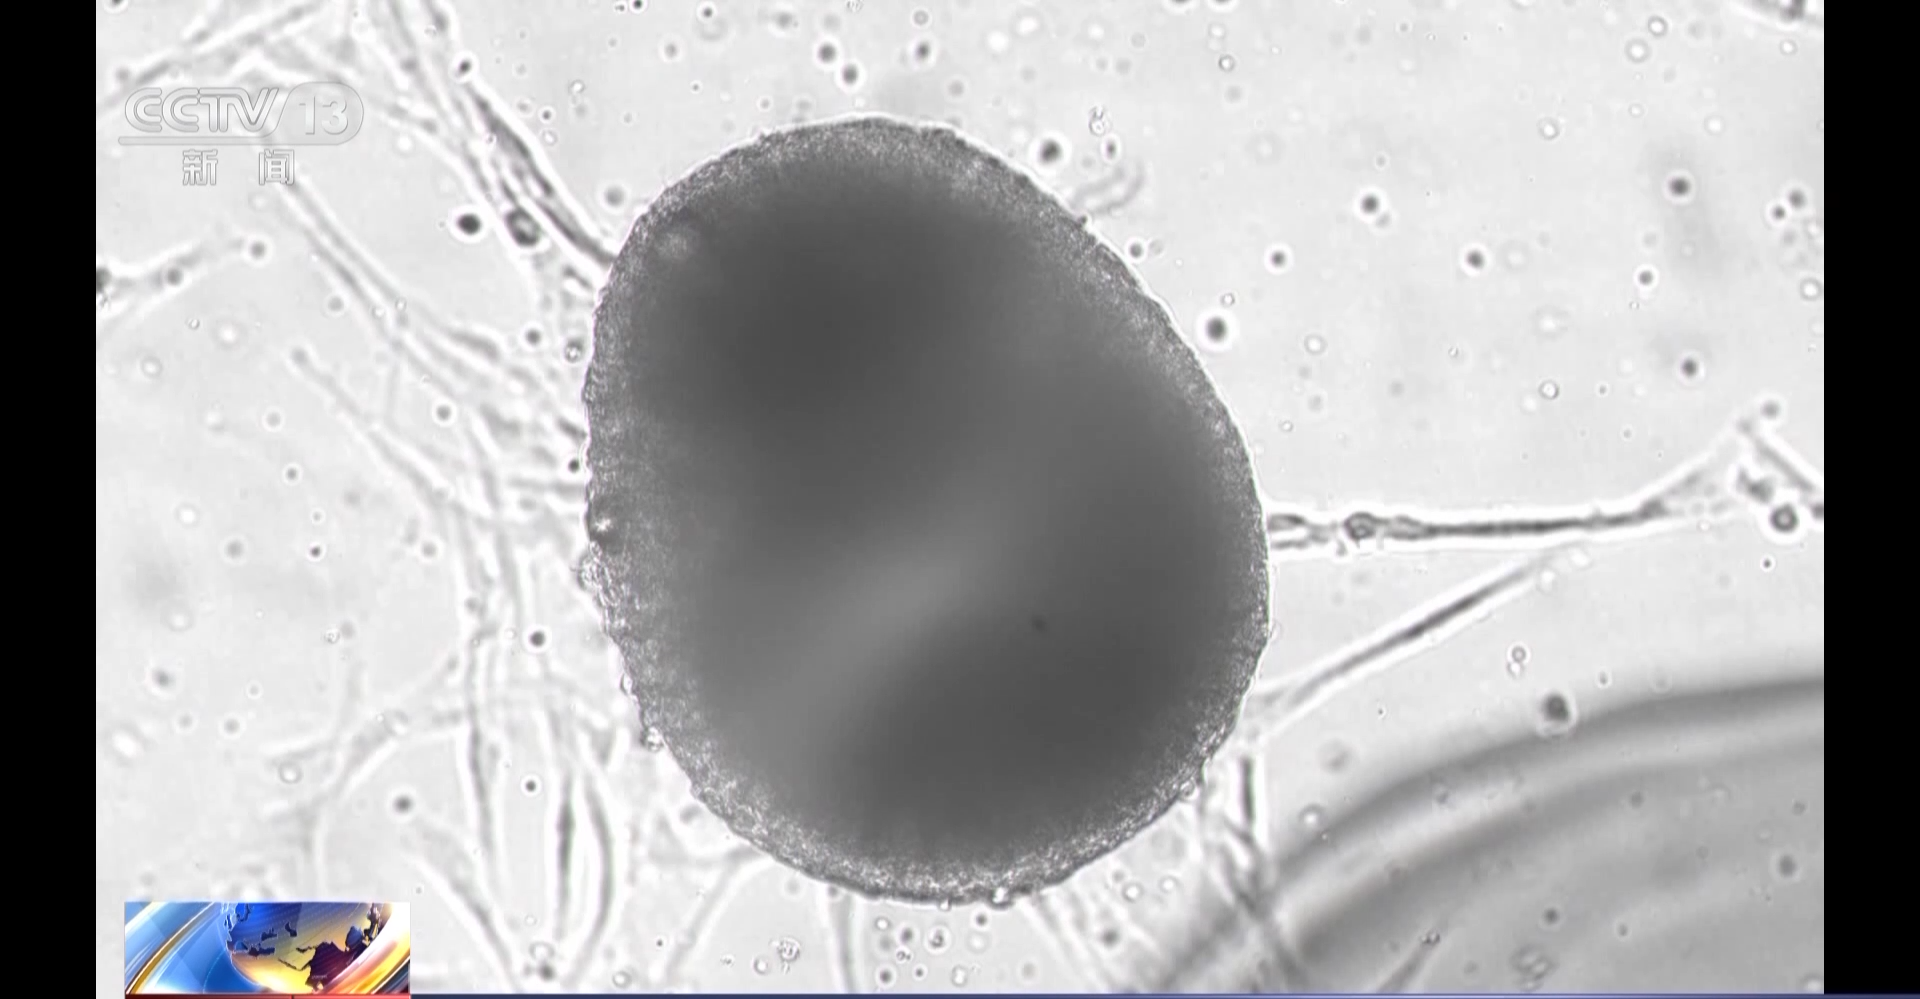

目前,我国已在轨实施了多个航天医学细胞学实验项目,不仅为航天员的身体健康防护提供了重要的研究平台,也可为大众健康作出贡献。

在轨细胞学实验为从器官、组织、细胞和分子水平研究空间失重等因素对机体的影响机制、开展针对性的防护等提供了理论和实验依据。在神舟十三号、十四号、十五号、十六号和天舟五号5次飞行任务中,将8种细胞和人工血管芯片送上太空,在轨共开展了10项细胞学实验研究,从在轨实验技术、实验模型和科学研究等多方面取得了系列创新性成果。

中国航天员中心研究员 航天员系统副总设计师 李莹辉:经过建设期这几次飞行任务的考验,建成了一个具备多功能长时程开展各类细胞研究的能力。最长的现在可以养到40天,这对细胞来说也是一个比较长的突破。我们建立一套非常适用空间条件下开展研究的实验体系,具备了在轨开展多种细胞培养、多种器官模型的实验和多种微环境体系下实验的能力。从建设期来说,具备了在轨开展细胞生理学研究的基本能力,骨骼、肌肉、心血管都有相应的系统和设备来开展研究,这对于更好认识在轨细胞发生的变化,提供了一个特别好的平台。

中国航天员科研训练中心研究员 谭映军:细胞培养单元,它包括我们细胞培养样本,能够自动取样、固定这一套完整的试剂,都在集成在一个小小的方盒里面。细胞培养单元,所以航天员上天以后需要安装在核心舱的培养装置里开展实验,一次能够安装13个这样的实验单元。培养装置是一个自动化的培养装置,能够自主建立满足航天一些实验需求的培养环境,包括温度和二氧化碳的浓度,设备中集成了一个重力对照的系统,能够在天上的实验期间形成建立一个0到2G的人工重力环境,满足空间重力对照的实验需求,同时还集成了一套在线的样本,显微观察记录装置,能够在实验期间记录自动记录样本的实验情况。

目前我国将人多能干细胞来源心肌细胞、皮肤干细胞、成骨细胞、人骨骼肌卫星细胞等细胞和人工血管芯片送上太空,在轨开展了微重力诱导心血管紊乱的细胞学机制及其防护药物筛选、空间微重力环境下皮肤干细胞的生物学效应与分子机制等细胞学实验研究。